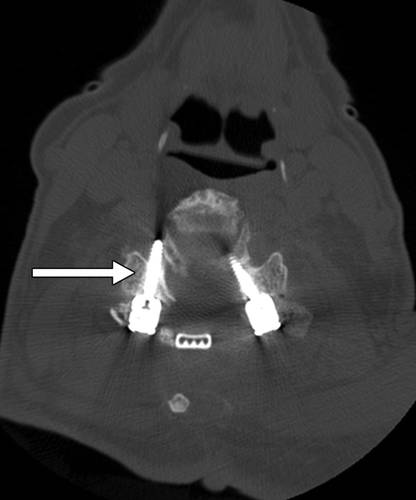

图2--78岁男子因颈部疼痛并广泛退行性变,接受颈椎融合。颈椎CT图像显示右侧C5关节螺钉(箭头)移位,在C5-C6处穿过右神经孔。